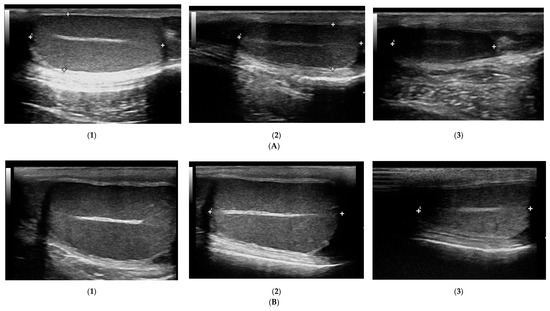

3.3. Testicles B-Mode Appearance